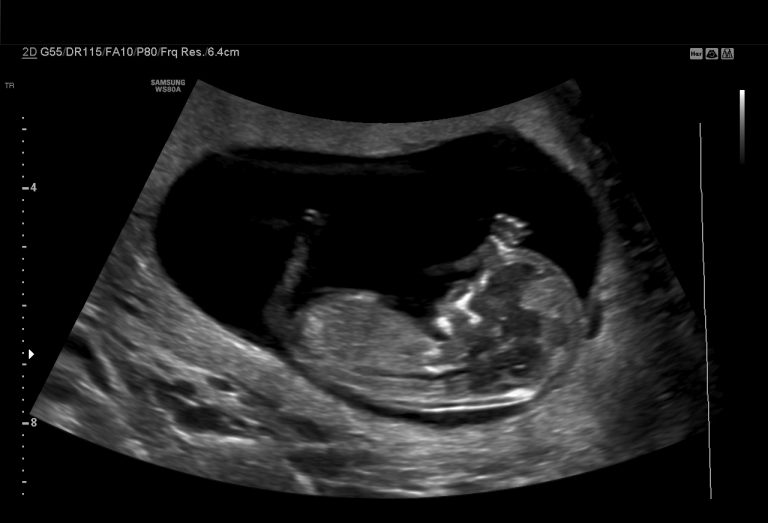

Level II Detailed Anomaly Scan (18–22 weeks)

Most important Fetal scan:

• Head-to-toe structural evaluation

• Heart, brain, spine, face, limbs, kidneys

• Placenta, amniotic fluid & cervix

• Soft markers review